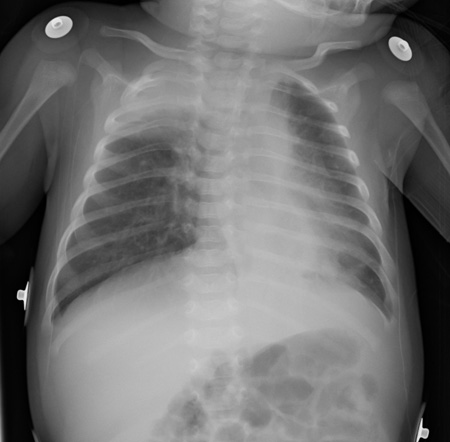

Respiratory syncytial virus infection

Air trapping and peribronchial cuffing

From the personal collections of Melvin L. Wright, DO and Giovanni Piedimonte, MD; used with permission